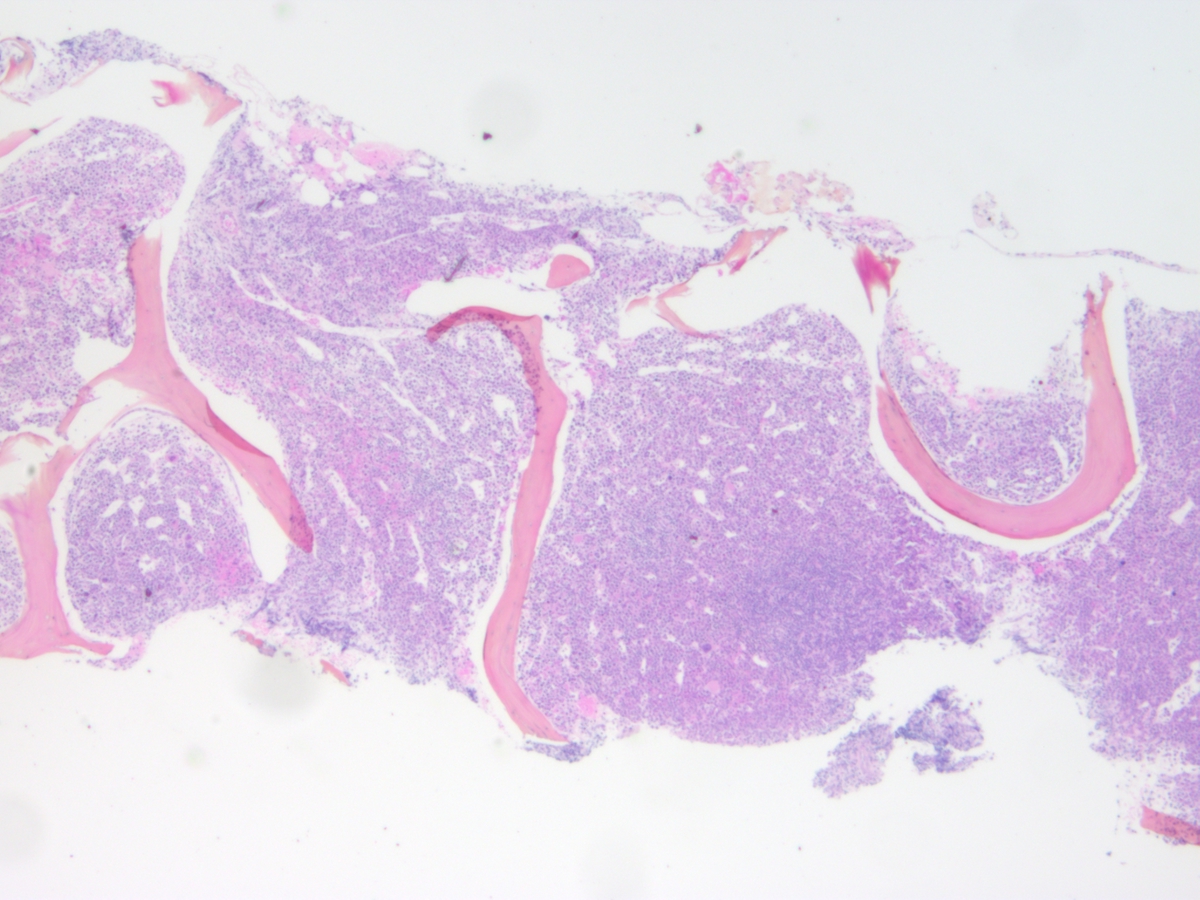

The peripheral blood film revealed a rare circulating blast and occasional partially degranulated basophils but with no absolute basophilia.The bone marrow aspirate was dilute and partially clotted but was hypercellular for age. 40% blasts were enumerated, with their morphological appearance being large with irregular nuclei, fine chromatin, occasional large nucleoli and small amounts of basophilic cytoplasm. Occasional granules were noted but no Auer rods were seen. A few degranulated basophils were also observed, similar to the peripheral blood. Erythropoiesis was markedly reduced with a mild reduction in megakaryocytes.The bone marrow biopsy was approaching 100% cellularity with sheets of immature mononuclear cells and scattered mitotic figures, representing blasts and left shifted myeloid cells. Erythropoiesis was markedly reduced with scattered unremarkable megakaryocytes. A couple of interstitial lymphoid aggregates were present in close association with small blood vessels, suggesting reactive aggregates.IMMUNOHISTOCHEMISTRY AND FLOW CYTOMETRY

| Bone marrow biopsy 2x | ![]() |

| Bone marrow biopsy 10x | ![]() |